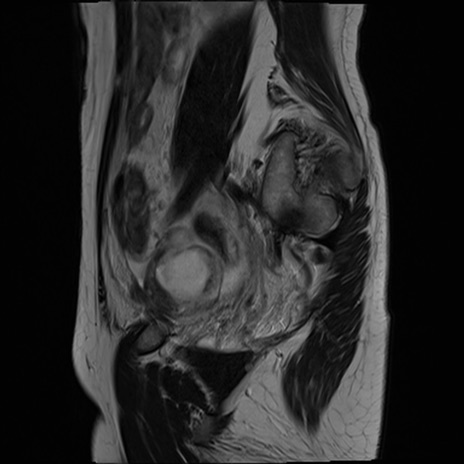

症例39 T2WI(矢状断像)

MRI(4日後)